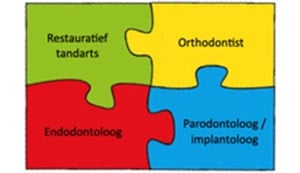

Complexe (parodontale) problematiek

Er is sprake van complexe parodontale problematiek wanneer parodontitis gecombineerd is met:

- Occlusaal trauma

- Drifting, flaring en toename van diastemen a.g.v. parodontitis

- Het verlies van 5 of meer gebitselementen a.g.v. parodontitis

- Het verlies van kauwvermogen

Niet zozeer het individuele element staat centraal, maar het mogelijk verlies van de dentitie als geheel

Behandeling van deze problematiek kan bestaan uit:

- Weghalen van storende contacten (fremitus) door selectieve occlusale aanpassingen

- Splinting door middel van een spalk, composiet of een brugconstructie

- Orthodontische behandelingen

- Partiële plaatprothese en frame-protheses

- Implantaat gedragen frame protheses

- Enkeltandsvervanging door een implantaat

- Brug op implantaten

- Volledige protheses, overkappingsprothese (met of zonder implantaten)